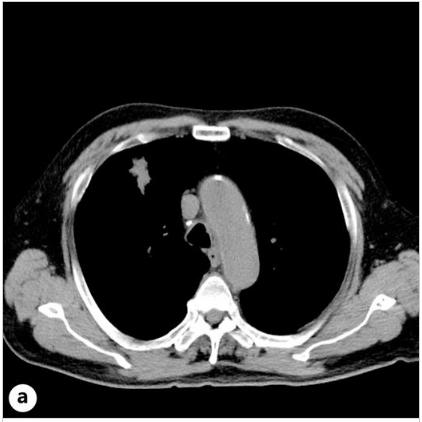

患者接受了卡铂/依托泊苷/杜伐单抗(Dur)和PEG-G-CSF的全剂量组合治疗,重点是剂量强度。在施用PEG-G-CSF后10天施用第四剂冠状病毒疫苗。在PEG-G-CSF给药后的第12天,出现38℃的发热和右耳疼痛,这种情况没有改善,并在第17天就诊。血液检查显示炎症反应明显升高,白细胞计数为15600/μL,C-反应蛋白为33.9 mg/dL,白细胞介素6 (IL-6)水平为114 pg/mL。然而,对整个躯干和头部的物理检查和简单的CT未能检测出发热源或炎症反应升高的原因(图一a)。虽然患者没有出现FN,但不能排除细菌感染的可能性,立即住院并使用了氨苄西林/舒巴坦。第二天对整个躯干进行的CE-CT显示主动脉弓降胸主动脉周围的脂肪组织密度增加,提示主动脉炎(图一b)。患者抗中性粒细胞胞浆抗体和其他自身抗体检测呈阴性。有乙型/丙型肝炎病毒(HBV/丙型肝炎病毒)感染史,入院后有退热趋势,并接受过ICIs治疗。因此,在没有全身皮质类固醇治疗的情况下,仅用解热镇痛药并进行了仔细的随访。第20天,患者体温改善至36°C,右耳疼痛和炎症反应逐渐改善,第33天的对比CT显示主动脉周围炎症表现改善(图一C,2)。那时血清IL-6水平降至8.7 pg/mL。由于免疫相关不良事件的可能性仍然存在,卡铂/依托泊苷的剂量减少到80%,Dur在第二个疗程的化疗中被停用。患者的病情进展顺利,除了白细胞计数略有下降。剂量减少的卡铂/依托泊苷以4周的间隔继续治疗,患者的进展良好,没有主动脉炎发作的迹象。

图1、患者的CT图像。A、PEG-G-CSF给药后第17天拍摄的胸部平面CT图像。此图像没有显示主动脉周围阴影增加。B、在PEG-G-CSF给药的第18天获得的胸部对比增强(CE)-CT扫描。此图显示主动脉周围阴影增加,提示主动脉炎。C、在PEG-G-CSF给药的第33天进行胸部CE-CT扫描。如图中的红色三角形所示,主动脉周围的阴影比图B中所示的要小